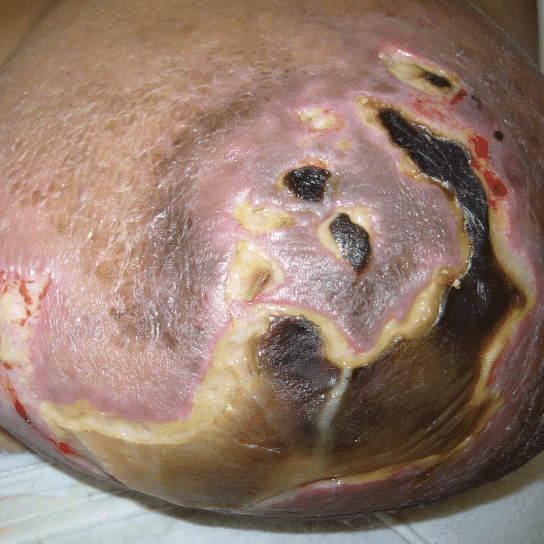

During pregnancy, it is treated by bromocriptine (an anti-prolactin agent) alternating with metformin (modulates insulin). Postpartum, patients should be given bromocriptine or cabergoline (anti-prolactin agent) before lactogenesis II (secretory activation, or “milk coming in”) to reduce the risk of skin necrosis (ulceration and death of skin). Donor milk or formula supplementation should be planned. Patients can later undergo elective breast reduction. The patient above is pictured below at end of pregnancy after being treated with lymphatic drainage and bromocriptine during pregnancy:

Improvement in lymphedema with lymphatic drainage and supportive bra/garment, just before delivery. Photo: Clara Farley, MD

While some cases of IGM may resolve from a simple mass, many go on to form fluid collections (above and below) that may drain on their own. These are mistakingly called “abscesses.” They are in fact just fluid collections of dead inflammatory cells. Patients need either local treatment with needle drainage of the fluid (NOT large incisions with packing tape, which make inflammation worse) and steroid injection, or oral steroids/anti-inflammatories/immune suppressants.